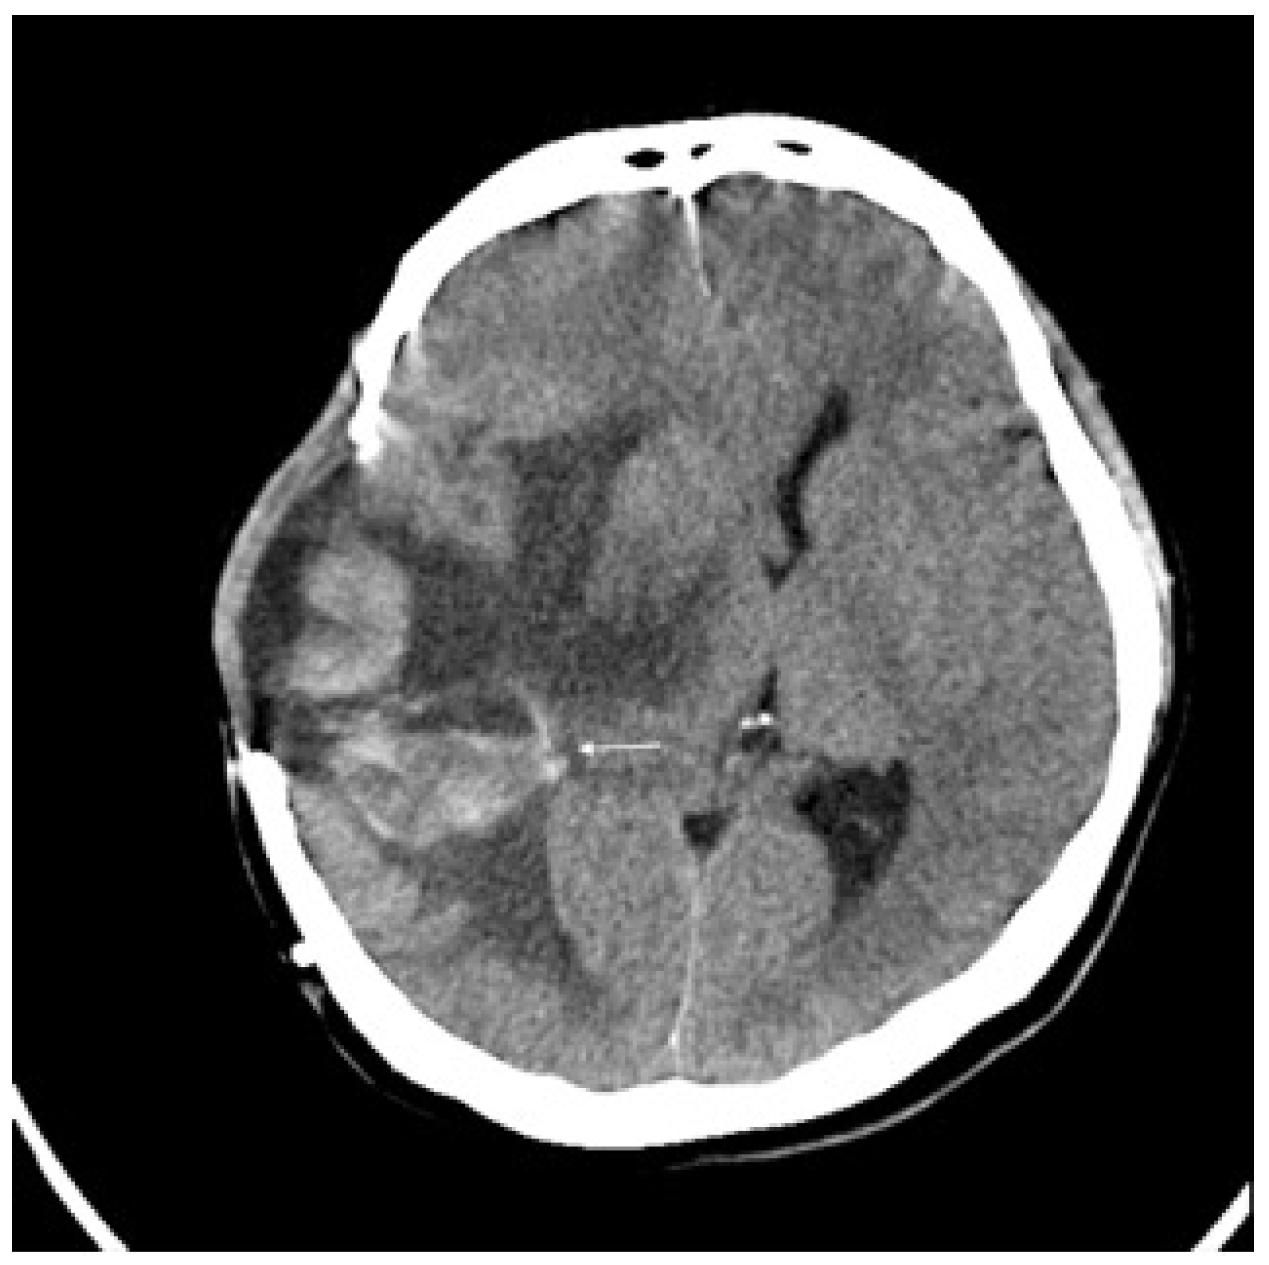

2. Detailed Case Description